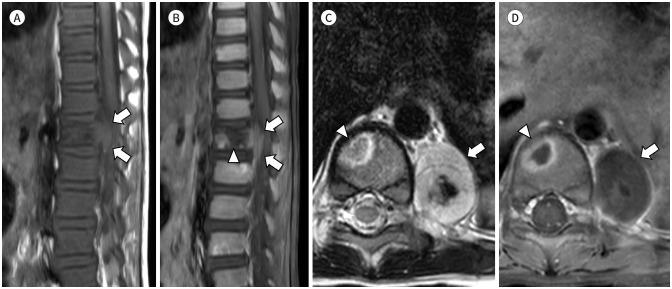

MRI plays a crucial role in bone marrow (BM) assessment, and has very high sensitivity in diagnosing marrow disorders. However, for radiologists who may not frequently encounter pediatric imaging, distinguishing pathologic BM lesion from normal BM can be challenging. Conditions involving the BM in pediatric patients, such as leukemia and metastatic neuroblastoma, often manifest with diverse musculoskeletal symptoms and may be diagnosed using musculoskeletal MRI examinations. Accurate interpretation of pediatric MRI requires not only an understanding of the normal composition of BM but also an awareness of agerelated developmental changes in the marrow and familiarity with conditions that commonly involve pediatric BM. We aim to describe the composition of normal BM and outline the normal and abnormal MRI findings in pediatric BM. Additionally, we aim to present clinical cases of malignant BM disorders including leukemia, neuroblastoma metastasis, and other malignant BM disorders.

磁共振成像(MRI)在骨髓(BM)评估中起着至关重要的作用,并且在诊断骨髓疾病方面具有很高的敏感性。然而,对于可能不经常接触儿科影像的放射科医生来说,区分病理性骨髓病变与正常骨髓可能具有挑战性。儿科患者中涉及骨髓的疾病,如白血病和转移性神经母细胞瘤,通常表现为多样的肌肉骨骼症状,可通过肌肉骨骼MRI检查进行诊断。准确解读儿科MRI不仅需要了解骨髓的正常组成,还需要认识到骨髓中与年龄相关的发育变化,并熟悉常见累及儿科骨髓的疾病。我们旨在描述正常骨髓的组成,并概述儿科骨髓的正常和异常MRI表现。此外,我们旨在展示包括白血病、神经母细胞瘤转移和其他恶性骨髓疾病在内的恶性骨髓疾病的临床病例。